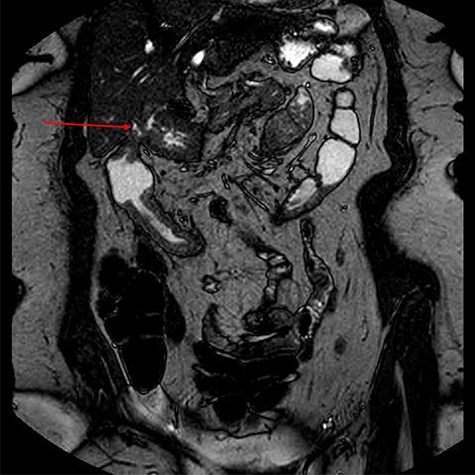

To further characterize, an endoscopic ultrasound demonstrated a fistula between the distal antrum and gallbladder containing air and possibly some tiny calculi or sediment. The common bile duct was of normal diameter. There was no lymphadenopathy and no obvious malignancy seen. Magnetic resonance imaging of the small bowel outlined the complex fistula, and non-specific changes in the colon, but provided no further information regarding aetiology (Fig. 4).